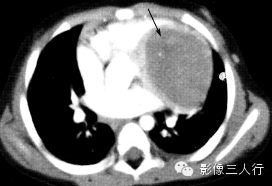

| 心房黏液瘤(图1) | 纤维瘤(图2) | 脂肪瘤(图3) | 横纹肌肉瘤(图4) | |

好发

年龄 |

成人 | 婴幼儿 | 成人 | 儿童或年轻人 |

部位 |

多起源于房间隔,以窄基底与其相连,并向心腔内生长 | 心室心肌内,常见于左室游离壁或室间隔 | 多原发于心外膜,在心房、心室无差异 | 各房室及间隔心肌壁均可发生,常累及一个以上心腔,可侵犯心包和大血管 |

病灶

形态 |

圆形或椭圆形,多呈浅分叶状,有蒂与心房间隔相连,肿瘤位置可随心动周期而变化,有时脱入左室 | 卵圆形或分叶状,常有薄层假薄膜,边界清楚 | 椭圆形或分叶状,边界清楚 | 形态不规则,边界不清,可见坏死、出血 |

CT

密度 |

稍低密度 | 密度稍低于心肌 | 脂肪密度 | 不均匀软组织密度 |

强化

特点 |

不均匀强化 | 强化程度较正常心肌弱 | 无强化 | 一般均匀强化,坏死后内部不强化 |